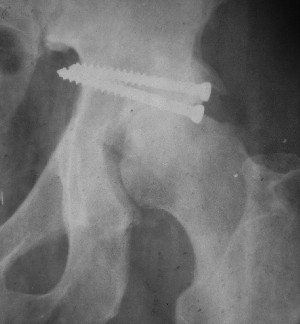

Послеоперационный снимок боковой 5/06/03

Больной 18 мая 2003 года в автоаварии получил перелом левой вертлужной впадины, вывих бедра. Госпитализирован в один из стационаров области.Вывих вправлен. В последствии бедро вывихивалось еще дважды. На консультацию был представлен снимок от 19.05.03г., больной переведен к нам 3.06.03г. Снимок при поступлении - перелом впадины, задне-верхний вывих бедра. 05.06.2003 г. выполнено открытое вправление вывиха левого бедра и остеосинтез стенки вертлужной впадины двумя винтами. Послеоперационный период без осложнений. Объем движений в левом тазобедренном суставе восстановился полностью. Выписан на амбулаторное лечение в удовлетворительном состоянии с рекомендациями 3 месяца ходить на костылях без нагрузки на оперированную конечность. На контрольных рентгенограммах левого тазобедренного сустава 13.10.2003 г. - признаки консолидации перелома; плотность, форма головки и состояние суставных поверхностей удовлетворительные. Разрешена дозированная осевая нагрузка, на конечность с использованием дополнительной опоры. 19.12.2003 г. больной обратился с жалобами на боли в левом тазобедренном суставе. На рентгенограммах левого тазобедренного сустава 19.12.2003 г., 20.02.04г. - асептичекий некроз головки бедра. 5.04.04г. - эндопротез. Сейчас ходит без трости, не хромает. Особенность эндопротезирования - при удалении винтов прослежена линия перелома заднего края впадины и предложено установить чашку несколько меньшего диаметра, чтобы она была покрыта несломанной частью.